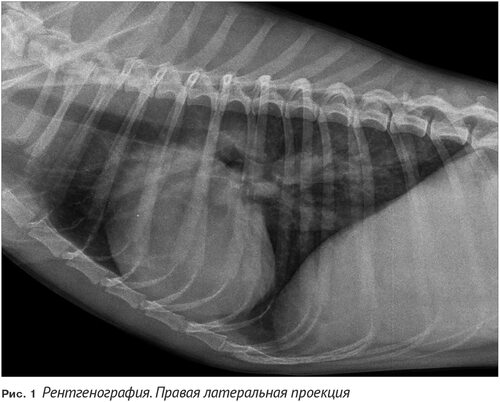

Ателектаз легкого у кошки рентген

Рентген грудной клетки кошки в норме

Легкие кошки снимок рентген

Бронхопневмония у кошек рентген

Пневмония у собак рентген

Коллапс трахеи у собак рентген

Бронхиальная астма у собак рентген

Кардиогенный отек легких у кошек рентген

Бронхит рентген снимок у собак

Диафрагмальная грыжа у кошки рентген